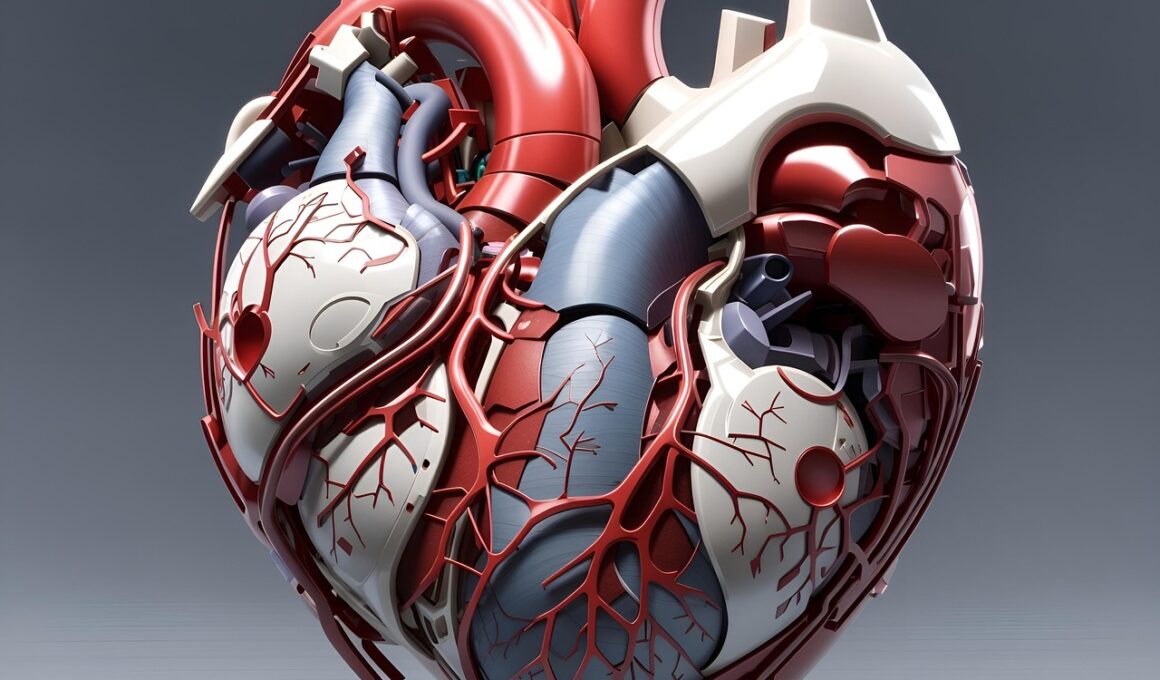

Sugar Detox and Cardiovascular Health: What You Need to Know

Sugar consumption plays a significant role in overall health, particularly in cardiovascular well-being. High sugar intake has been linked with increased risk of heart disease, hypertension, and obesity. Removing sugar from your diet can help reduce these risks and promote heart health. By eliminating refined sugars, one can experience several benefits, including improved insulin sensitivity, decreased inflammation, and better blood pressure management. Sugar detox programs encourage individuals to cut down on sugary snacks, beverages, and processed foods to facilitate a healthier diet. When you embark on a sugar detox, it fuels the body with healthier options such as fruits, vegetables, and whole grains. Incorporating these foods into your detox program can contribute to better cardiovascular health. The journey can be challenging, but staying mindful of sugar intake and overall diet is crucial. In this article, we will explore the impact of sugar on cardiovascular health and provide insights into effective sugar detox programs. Understanding these links can empower you to make informed dietary choices and foster long-term health benefits for your heart and overall well-being.

Reducing sugar intake provides an extensive range of health benefits, particularly concerning cardiovascular health. Studies have suggested that a diet low in added sugars contributes to weight loss and helps maintain a healthy weight. Weight management is critical as obesity is a known risk factor for developing heart disease. Furthermore, lower sugar intake fosters improved cholesterol levels and blood pressure regulation, both essential for heart health. As you detox from sugar, you may notice changes in your mood and energy levels, leading to enhanced productivity and emotional well-being. Several individuals report experiencing a reduction in cravings after the initial detox period, allowing for better control over their food choices. Additionally, a balanced diet rich in nutrients can bolster the immune system and reduce inflammation linked to cardiovascular diseases. Incorporating healthy fats, proteins, and fibers into your diet during the detox can ensure sustained energy levels and promote health overall. As you focus on these dietary changes, you may gain motivation and positive reinforcement, contributing to a healthier lifestyle that supports your heart health.

Another essential aspect of participating in a sugar detox program is the role of physical activity. Regular exercise complements your dietary changes, enhanced by a reduction in sugar consumption. Engaging in physical activities helps maintain cardiovascular fitness while aiding in weight management. Exercise promotes a healthy heart by strengthening cardiac muscles, promoting blood circulation, and regulating cholesterol levels. Combining exercise with a lowered sugar intake can lead to greater energy levels and improved overall health. Begin incorporating different forms of exercise into your routine, including aerobic exercise, strength training, or flexibility workouts. Aim for at least 150 minutes of moderate aerobic activity each week, along with strength-training exercises twice weekly. The positive impacts of exercise, coupled with a sugar detox, create a synergistic effect resulting in enhanced cardiovascular health. Setting realistic fitness goals can keep you motivated as you navigate challenges. Sharing your fitness journey with others can lead to increased accountability and lasting changes, supporting the detox process while fostering a community of heart-healthy individuals.